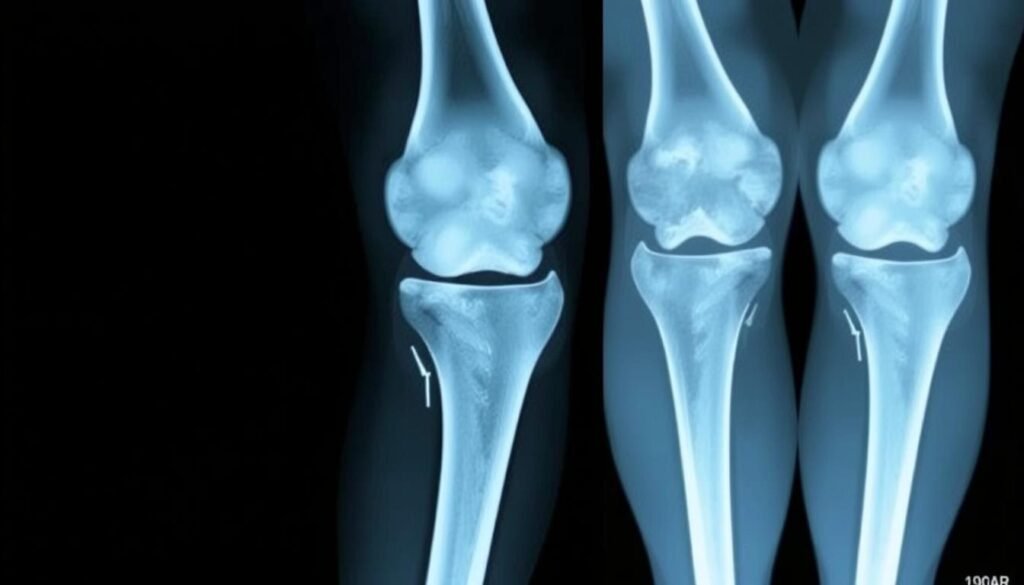

- Radiologisch nachgewiesene fortgeschrittene Arthrose (Grad III-IV)

- Starke Verschmälerung des Gelenkspalts im Röntgenbild

Röntgenbild einer gut integrierten Knieprothese 10 Jahre nach Implantation